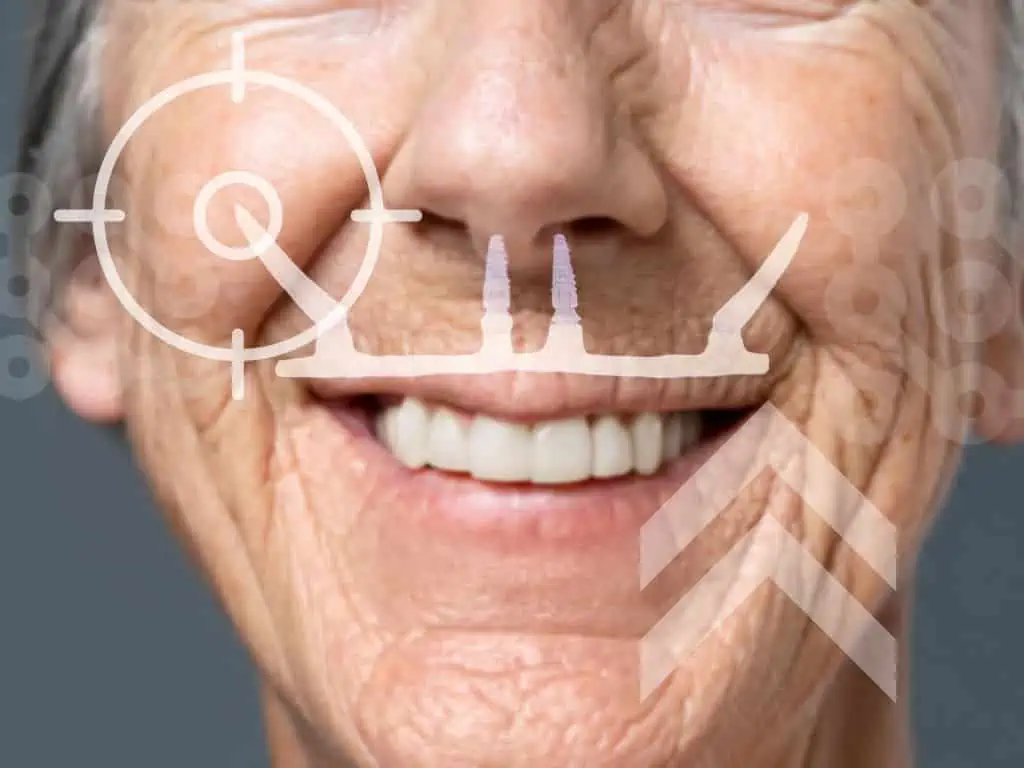

Prótese Protocolo: A Solução para Quem Usa Dentadura

A Prótese Protocolo é uma reabilitação completa e fixa sobre 4 a 6 implantes. Diferente das dentaduras convencionais, ela não possui “céu da boca”, não se movimenta ao falar ou comer e devolve 100% da força mastigatória. Disponível em cerâmica ou resina de alta resistência.

Técnica All-on-4

Uma alternativa moderna e eficaz para quem possui pouco osso. Esta técnica utiliza apenas quatro implantes posicionados estrategicamente para suportar uma prótese fixa completa, muitas vezes eliminando a necessidade de enxertos ósseos complexos e reduzindo o tempo total do tratamento.